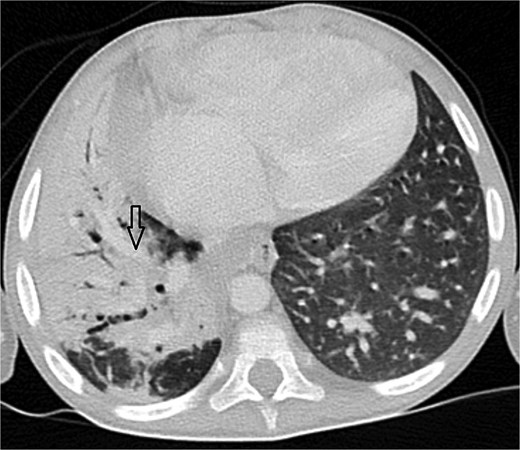

Axial abdominal CT showing central liver and polysplenism, compatible with left isomerism.

Urgent transthoracic echocardiography demonstrated a large echodense mass in the right hemithorax, compression of the right atrium and reduced flow through the right-sided shunt. Computed tomography angiography (CTA) confirmed a massive saccular pseudoaneurysm (≈8 × 7 × 6 cm) arising from the anastomosis between the right subclavian artery and the mBTTS graft, completely thrombosed without active contrast extravasation (Fig. 1). There was complete thrombotic occlusion of the right pulmonary artery, right lung collapse due to extrinsic compression and right lower-lobe consolidation consistent with pneumonia (Fig. 2). CTA also revealed left isomerism with central liver and polysplenism (Fig. 3) and a horseshoe kidney (Fig. 4), suggesting a previously unrecognized polymalformative syndrome.